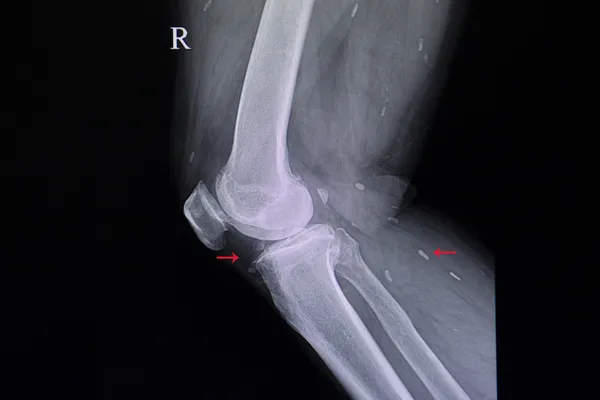

Diz kireçlenmesindeki tedavi seçeneklerini anlatan Dr. Öğr. Üyesi Bağçacı, "Eklem kireçlenmesi sadece eklem kıkırdağının değil, aynı zamanda eklemde yer alan kıkırdak altındaki kemik dokusu, eklem kapsülü, eklem civarında yer alan kaslar gibi yapıların bozulması, yıpranması sürecini içeren düşük doz iltihaplanma ile giden eklem hastalığıdır. Eklemde oluşan mekanik hasarı vücut-eklem iyileştirmeye çalışmaktadır. Nasıl insanın saç tellerinde beyazlaşma ortaya çıktığı zaman eski halini alması muhtemel değilse, artroz ortaya çıkınca insanlarında kıkırdak dokusunun eski halini almasını beklemek de yanlış olur. Günümüzde kıkırdak dokunun onarımına katkı sağlayan çeşitli tedaviler mevcuttur" şeklinde konuştu.

Diz kireçlenmesi için hastalığın seviyesine göre uygulanabilecek çeşitli tedavi yöntemlerinden bahseden Dr. Öğr. Üyesi Sinan Bağçacı, ''PRP, CGF, sitokinden zengin plasma, otolog konsantre prp gibi serum uygulamaları diz kireçlenmesinin seviyesine göre uygulayacağımız tedavi seçeneklerindendir. Bu uygulamalardaki amaç; etkilenen dokuda serum içerisinde bulunan sitokinler ve hücresel elemanların iyileşmeyi uyarıcı etkisinden faydalanmaktır. PRP hücresel içerik olarak çok az kırmızı kan hücresi ve yoğun kan pulcuğu içerir. Sitokinden zengin plasma ise hücresel içeriğe sahip değildir. Sitokinden zengin (akıllı plasma ) eklemde var olan yangısal reaksiyonu daha fazla azaltmaktadır" dedi.

Erken evre diz kireçlenmesi hastalarında karın ya da kemik iliği kaynaklı kök hücre uygulamalarında oldukça iyi sonuçlar alınabildiğini kaydeden Bağçacı, ileri yaşta ve dizde sıvı kaybının, lubrikasyon azalması varlığında eklem içine hyaluronik asit uygulamasının da iyi bir seçenek olduğunu kaydetti. Diğer bir tedavi seçeneği olan Proloterapi uygulamasından bahseden Bağçacı, "Bu uygulama hem eklem kıkırdağında onarım yapabilir hem de ekleme destek olan bağ dokuların kalınlığının artışını ve onarımını sağlar. Diz kireçlenmesinde eklem kıkırdağının yapısının korunması ve onarımını hedef alan tedaviler yanında eklemi destekleyen yapılar ve kaslar güçlendirilmelidir. Denge artırıcı egzersizler tedavide yer almalıdır'' diye konuştu.